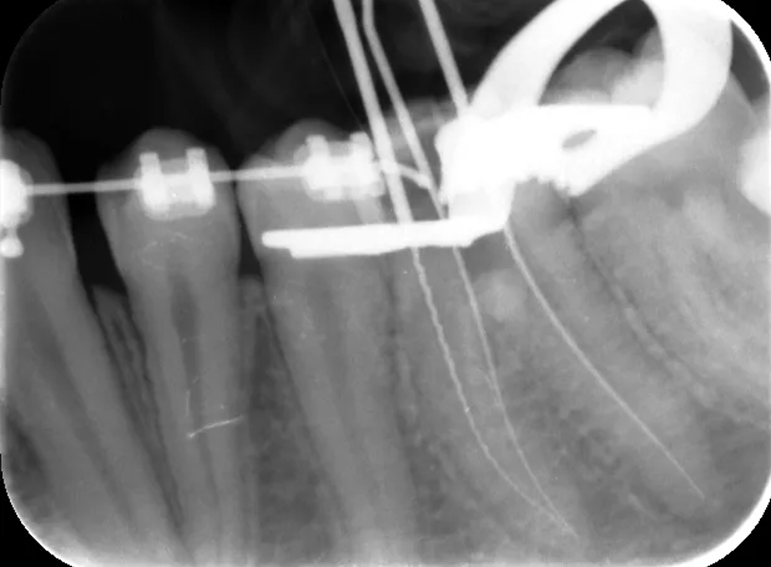

Root filling revision of a lower molar.